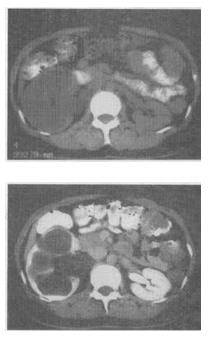

- 单项选择题 患者,女,46岁。消瘦、右腰部疼痛2个月余,伴血尿2。天,CT图像见图,最有可能的诊断是()。

- D